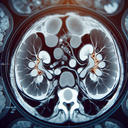

МРТ нирок

Магнітно-резонансна томографія (МРТ) нирок — це неінвазивне дослідження, яке використовує магнітне поле та радіохвилі для отримання детальних зображень нирок і прилеглих структур. ### Коли проводиться МРТ нирок: 1. **Підозра на захворювання:** - Пухлини або новоутворення - Кісти - Інфекції або запальні процеси 2...